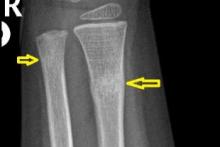

3-latek po urazie przedramienia prawego - kontrola po zdjęciu gipsu

Przypadek 60: 3-latek po złamaniu przynasad dalszych obu kości przedramienia prawego. Badanie kontrolne po zdjęciu gipsu (4 tyg. po urazie).

Rozpoznanie: Na zdjęciach RTG widoczne nawarstwienia okostnowe / odczyny naprawcze w miejscu złamania prawej kości promieniowej, z jej niewielkim kątowym ustawieniem. Niewielkie nawarstwienia okostnowe w okolicy złamania prawej kości łokciowej.